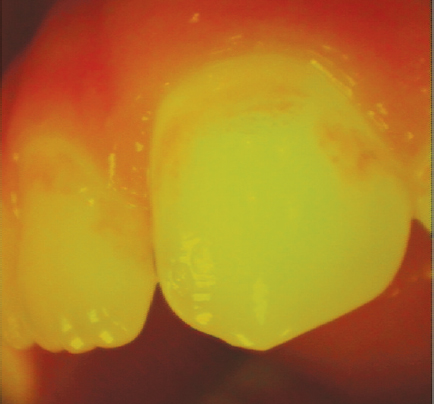

Oral cavity sanitation was performed in all patients before and during the installation of the bracket system and the stages of treatment. The average treatment period was no longer than 30 months. Caries intensity was assessed after oral cavity sanitation. The “D” component included caries in staining stage K02.0. Noncarious enamel defects, classified in ICD10 under codes K00.4 and K00.5, were also noted. Patients with confirmed diagnoses of dental fluorosis (K00.30) were excluded according to the criteria. The differential diagnosis between carious and noncarious stains was made using vital staining and fluorescence diagnostics after plaque removal. If staining was not detected and porphyrin fluorescence was absent, enamel defects (K00.4 and K00.5) were noted. If staining was detected and porphyrin fluorescence was present, caries (K02.0) was noted. Methylene blue solution was used for staining, and VistaCam was used to determine fluorescence (Figs. 1 and 2).

Fig. 2. Stain with signs of demineralization in the subsurface layer (caries, K02.0)

Рис. 2. Пятно с признаками деминерализации в подповерхностном слое (кариес К02.0)